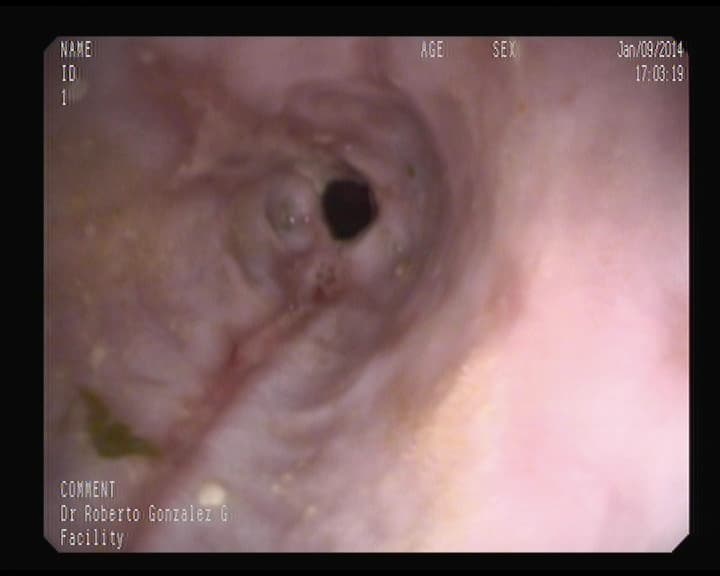

Otra cara de un orificio apendicular normal

Orificio apendicular visto desde el intestino grueso, sin signos inflamatorios.

Visión del orificio apendicular en ciego.

Ese orificio oscuro, es la entrada del apéndice.